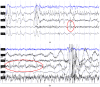

In addition to characteristic and easily identifiable behavioural signs-namely epileptic seizures-electroencephalography (EEG) has long been a standard component of epilepsy diagnosis protocols. In veterinary practice, EEG is typically performed in a semi-invasive manner, using subcutaneous electrodes and sedation. Here, we propose that the non-invasive polysomnography protocol, originally developed for basic research, can serve as a more welfare-friendly yet informative alternative for assessing epileptic brain activity in dogs. In this study, N = 11 family dogs diagnosed with epilepsy underwent a single non-invasive polysomnography session. EEG-based evidence for epileptic activity was detected in two cases. Polysomnography data from these 11 epileptic dogs were further analysed to evaluate sleep structure parameters. Compared to a matched control group of N = 11 clinically healthy dogs, the epileptic group exhibited reduced sleep efficiency, increased sleep latency, more wakings after sleep onset, and less time spent in drowsiness and non-REM sleep. These findings support the potential utility of non-invasive brain monitoring techniques, such as polysomnography, in the diagnosis and management of epilepsy in veterinary medicine.